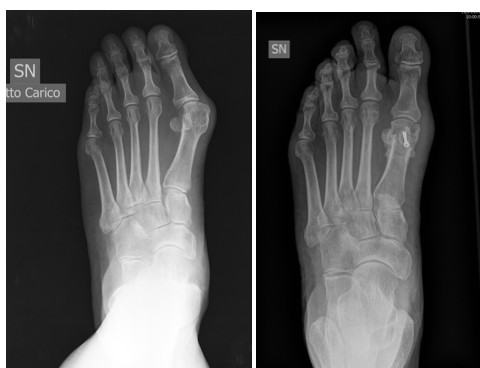

Alluce valgo

Una volta che l’alluce devia dal suo asse rettilineo, e punta sempre più in direzione del quinto dito, si parla di deviazione in “valgo”. Questo crea inevitabilmente una sporgenza ossea all’interno del piede, nota anche come “cipolla”.